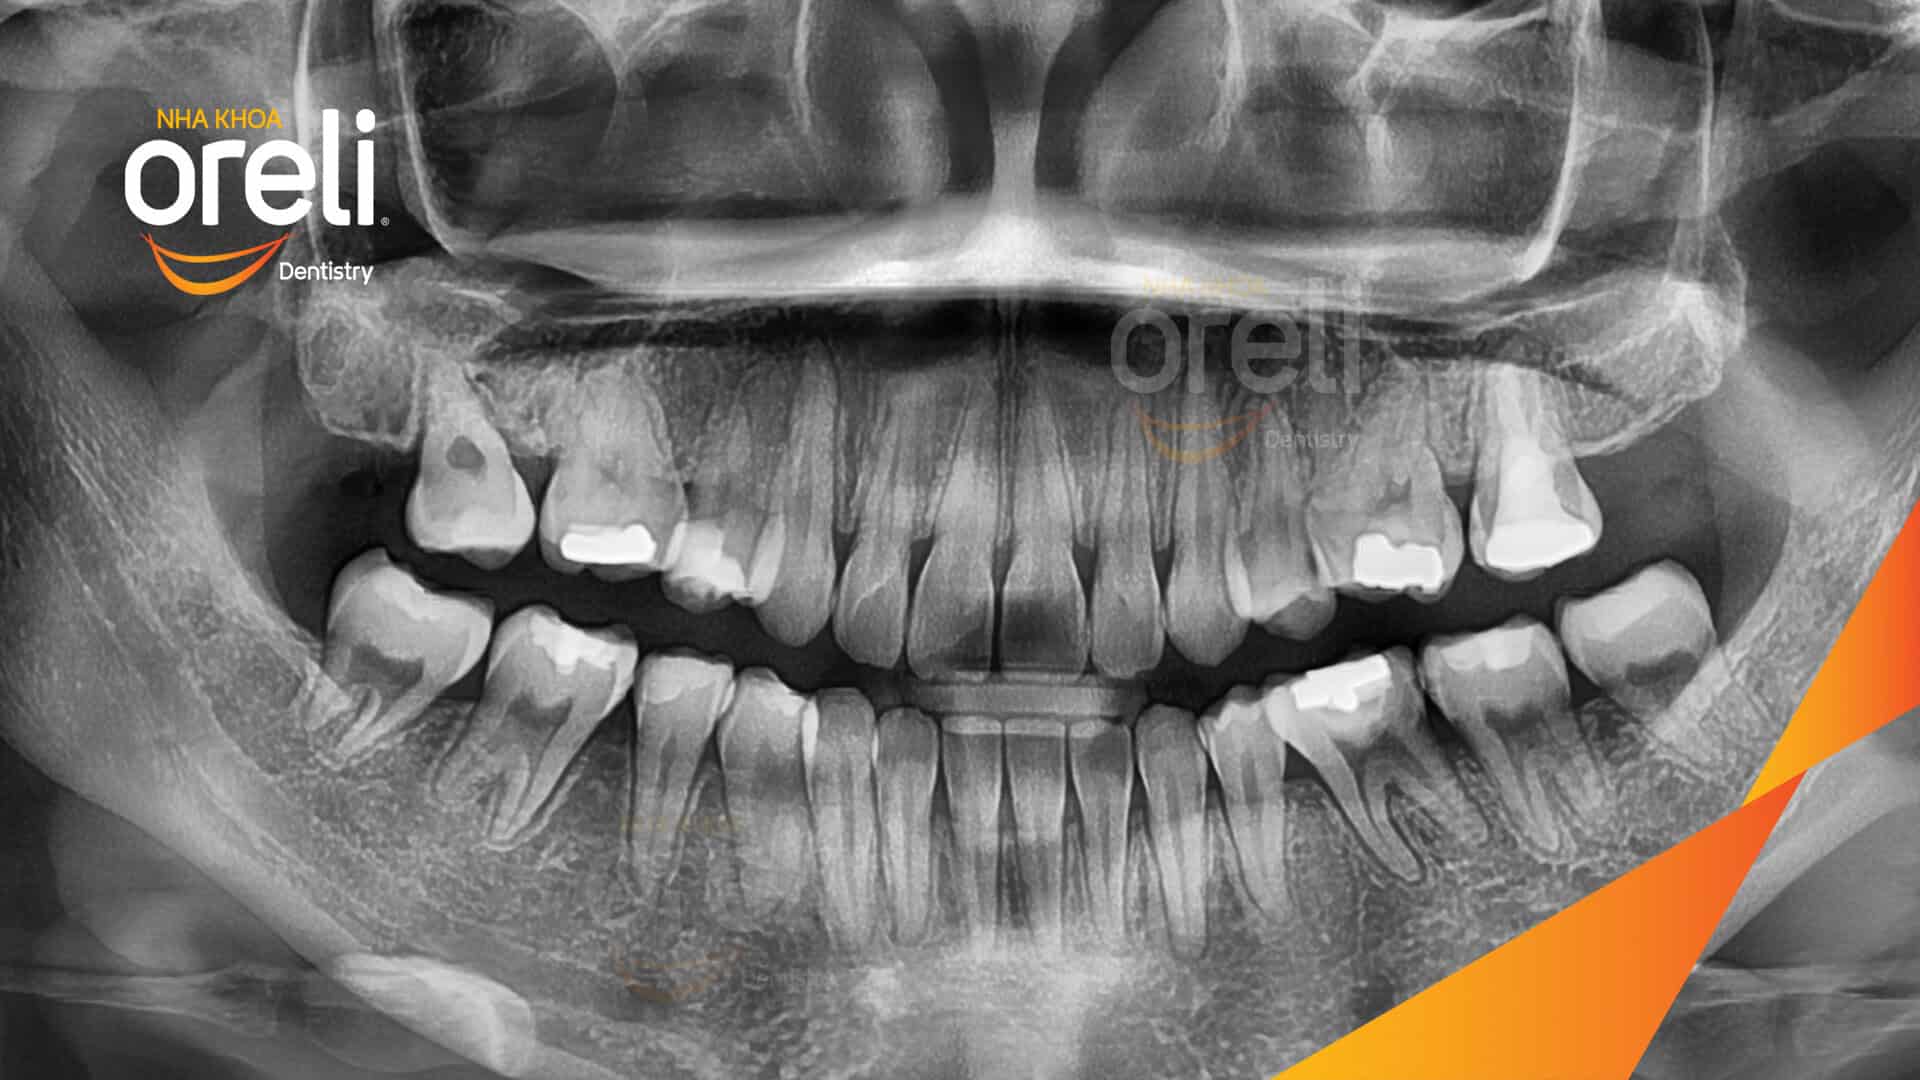

Ca niềng răng sai khớp cắn hạng 3 móm chen chúc kèm di gần răng số 7 8 thay thế răng 6 ở Oreli Niềng răngChen chúcDi gần răng 7 8Móm Xem thêm